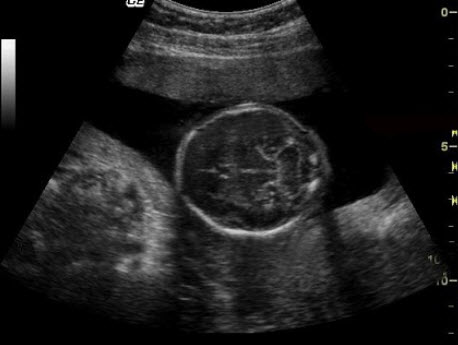

如图,为一胎儿中脑-小脑切面,胎儿应该属于早、中、晚孕哪一阶段______。

• 如图,为一胎儿中脑-小脑切面,胎儿应该属于早、中、晚孕哪一阶段______。